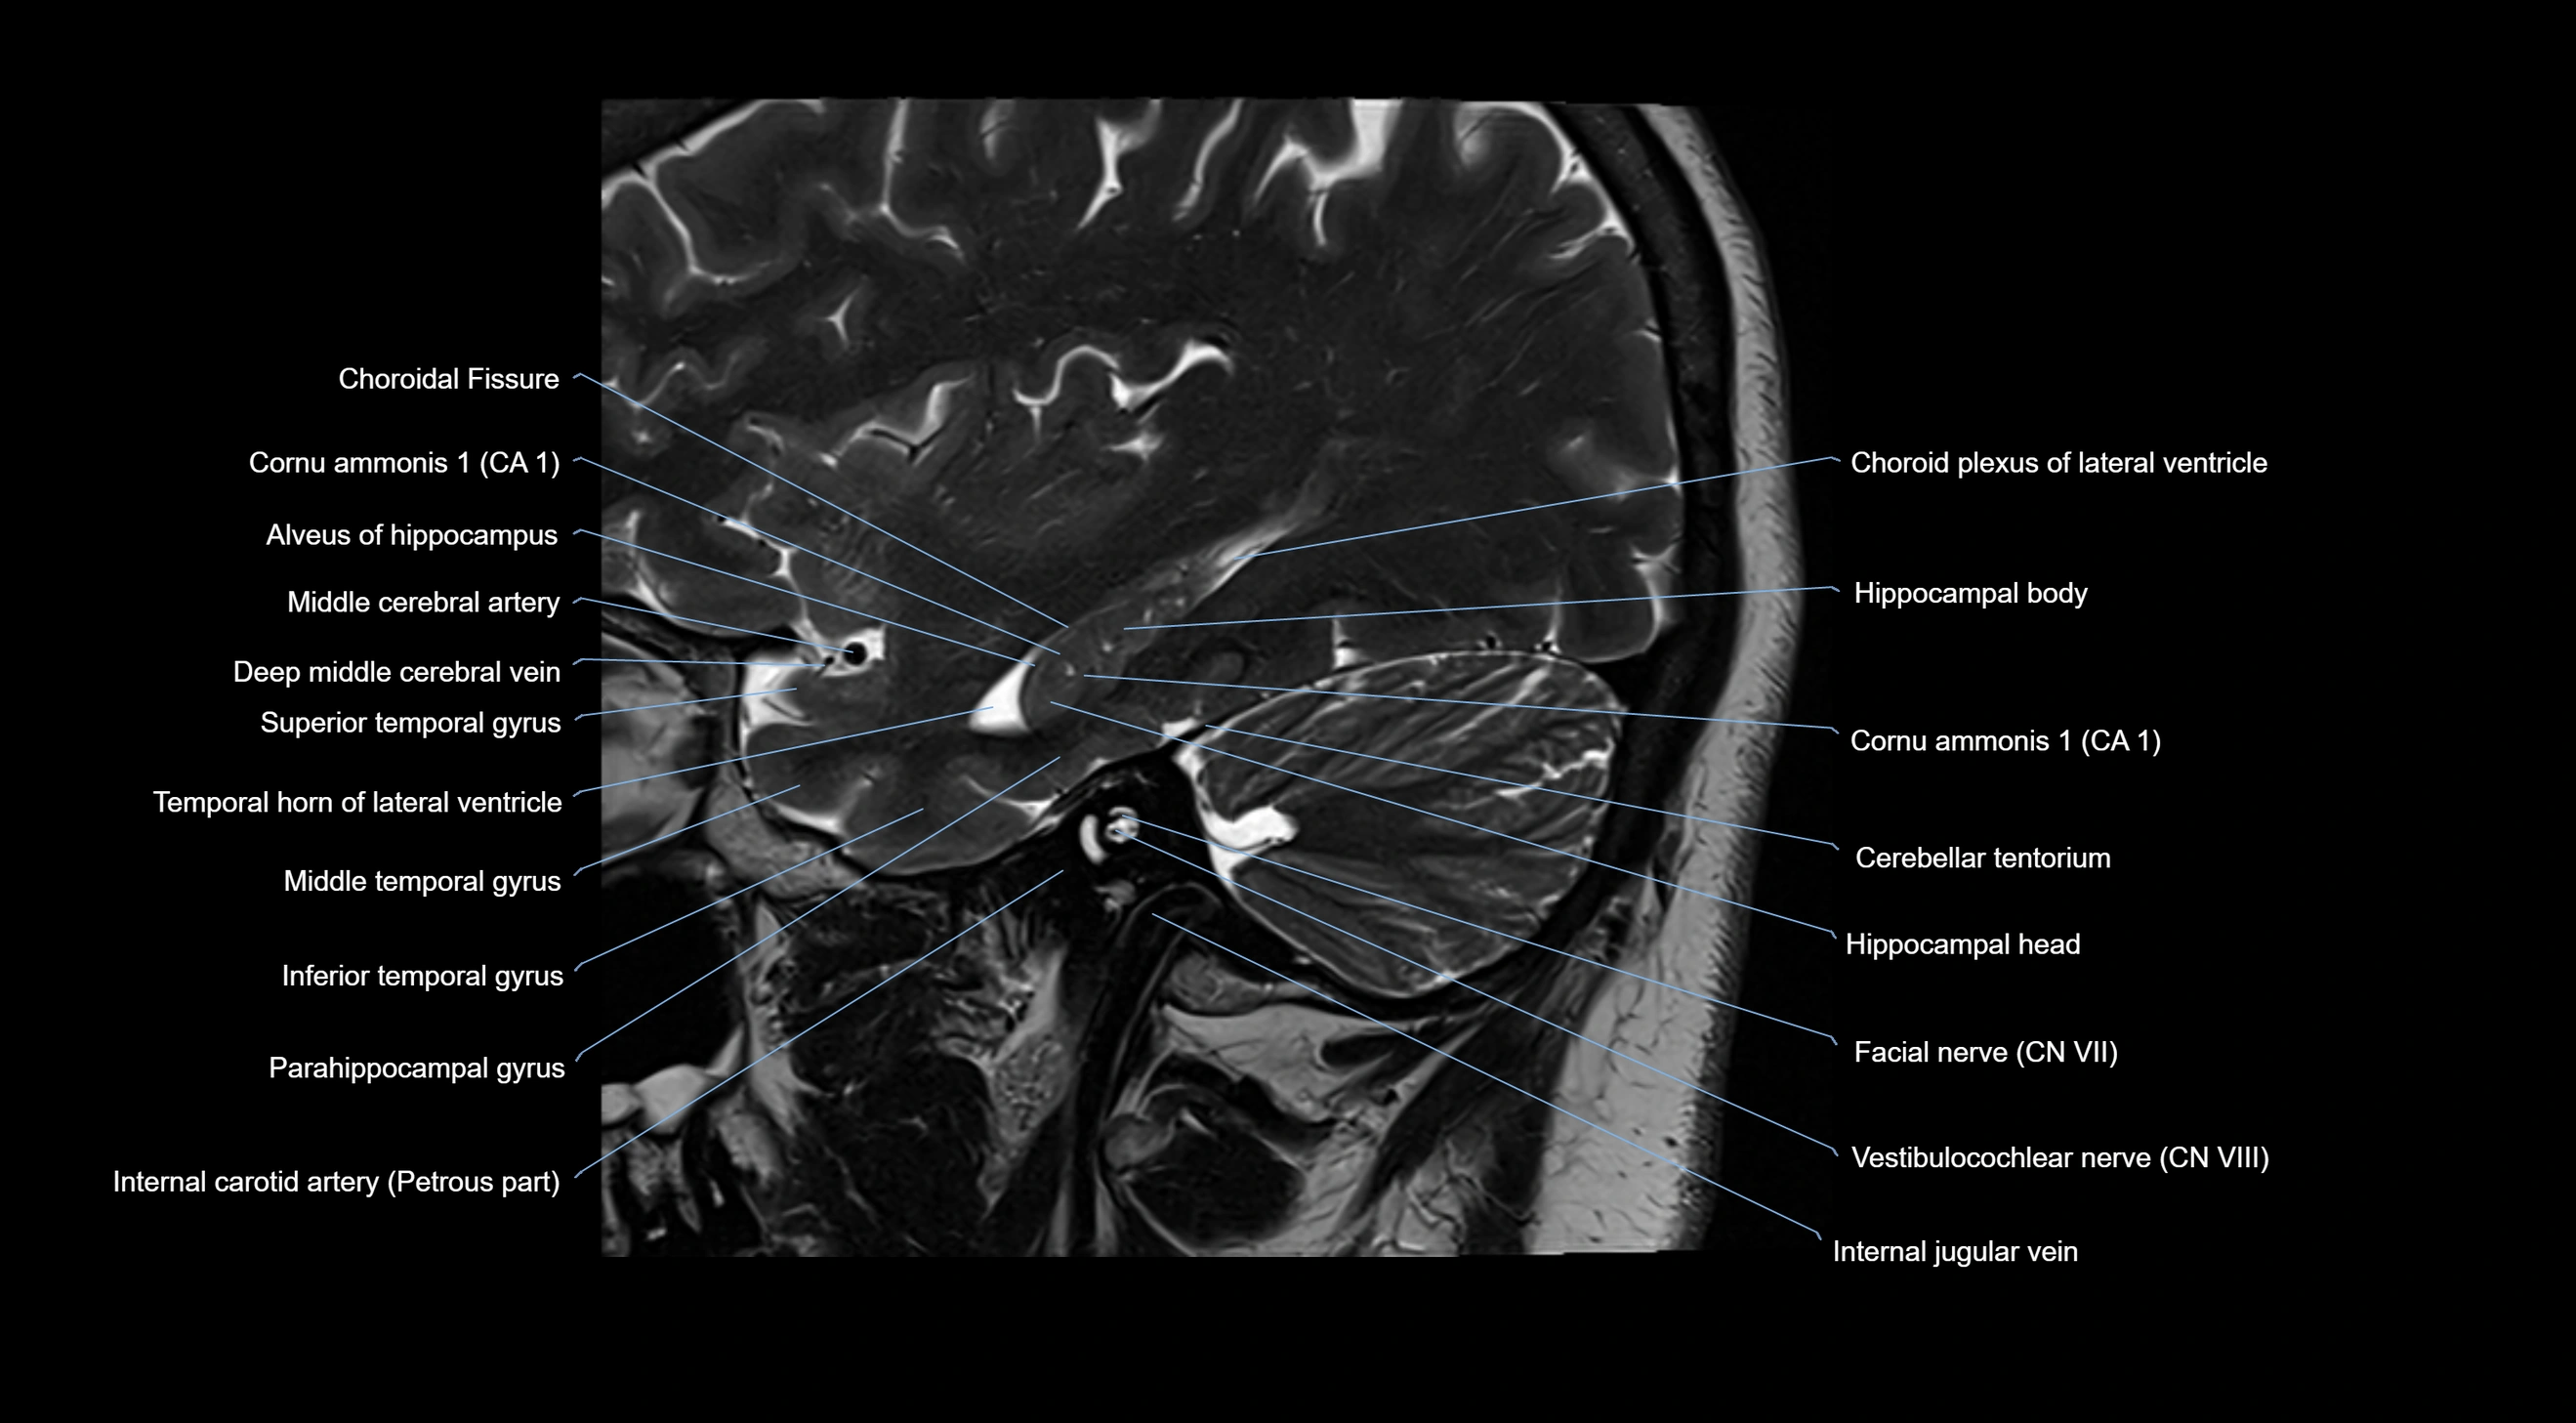

- Choroid fissure

- Choroid plexus of the lateral ventricle

- Facial Nerve (Cranial nerve VII)

- Internal carotid artery

- Internal jugular vein

- Middle cerebral artery

- Pes hippocampi

- Petrosal vein

- Temporal horn of lateral ventricle

- Vestibulocochlear nerve (Cranial nerve VIII)